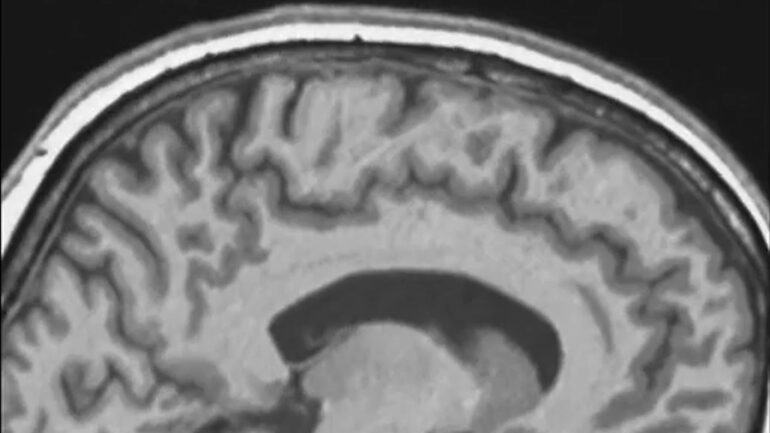

Without gravity pulling downward, the brain floats in the skull and experiences various forces from the surrounding soft tissues and the skull itself. Earlier studies showed that the brain appears higher in the skull after spaceflight. But most of those studies focused on average or whole brain measures, which can hide important effects within different areas of the brain.

We analyzed brain MRI scans from 26 astronauts who spent different lengths of time in space, from a few weeks to over a year. To focus on the brain’s movement, we aligned each person’s skull across scans taken before and after spaceflight.

That comparison allowed us to measure how the brain shifted relative to the skull itself. Instead of treating the brain as a single object, we divided it into more than 100 regions and tracked how each one had shifted. This approach enabled us to see patterns that were missed when looking at the whole brain, on average.

We found that the brain consistently moved upward and backward when comparing postflight to preflight. The longer someone stayed in space, the larger the shift. One of the more striking findings came from examining individual brain regions.

In astronauts who spent about a year aboard the International Space Station, some areas near the top of the brain moved upward by more than 2 millimeters, while the rest of the brain barely moved. That distance may sound small, but inside the tightly packed space of the skull, it is meaningful.